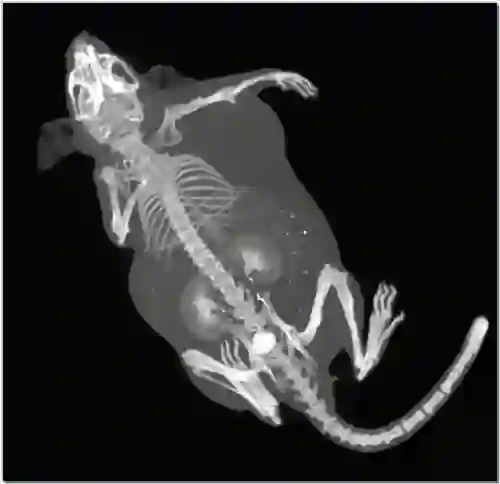

应用二:肿瘤模型鼠全身扫描(碘对比剂)